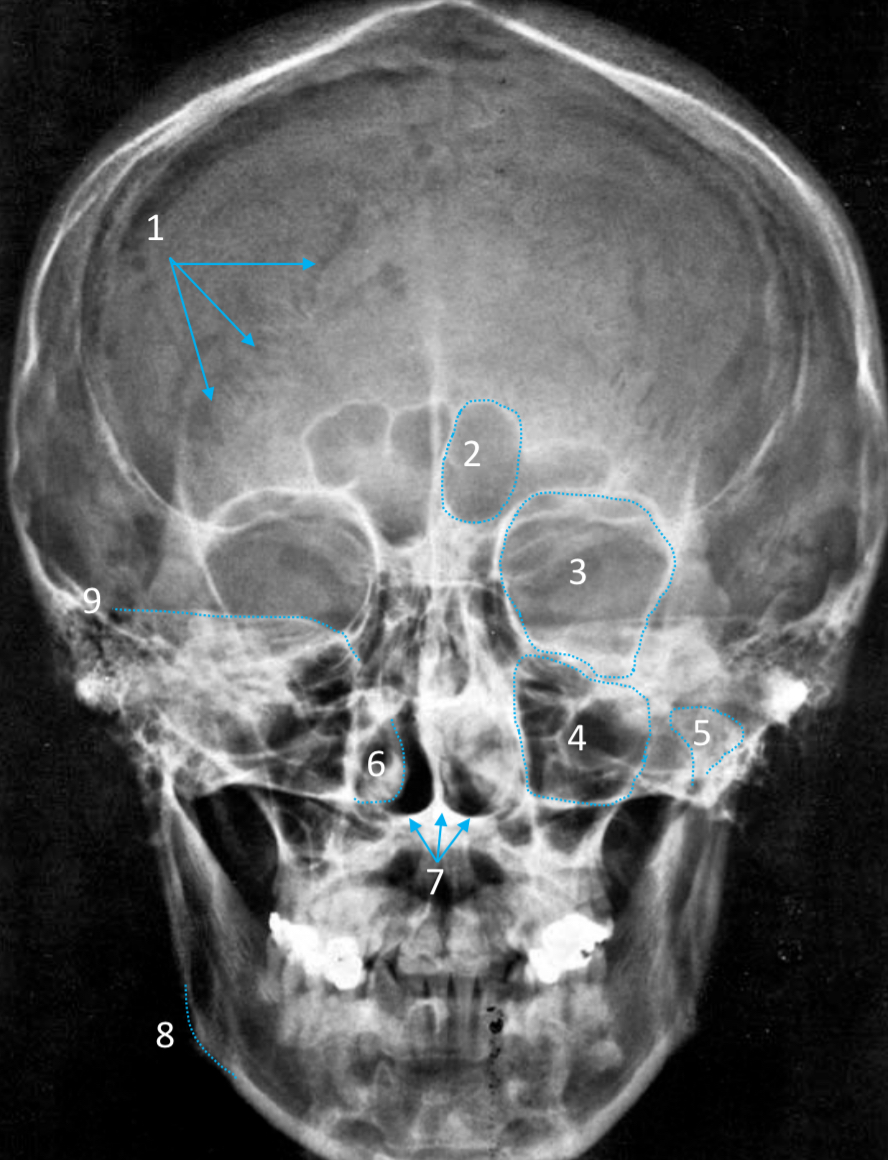

Frontal sinus

ID structure

Pituitary fossa

ID structure

Frontal sinus

ID structure

Orbital margin

Orbit

Maxillary sinus

ID structure

Mandibular condyle

ID structure

Inferior nasal concha

ID structure

Hard palate

ID strucutre

Gonial angle

ID strucutre

Petrous ridge

ID structure

Groove of middle meningeal a.

ID structure

Roof of orbit

ID structure

Frontal sinus

ID structure

Pituitary fossa

ID structure

Petrous ridge

ID structure

Sphenoid sinus

ID structure

Hard palate

ID structure

Mastoid air cells

ID structure

Zygomatic arch

ID structure

Mandibular condyle

ID structure

External auditory meatus

ID structure

Mastoid air cells

ID structure

Foramen magnum

ID structure

Foramen ovale

ID structure

Foramen spinosum

ID structure